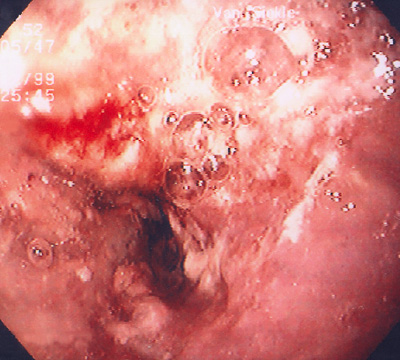

A history of smoking and/or alcoholism is often present in patients with esophageal squamous carcinoma, while a history of Barrett esophagus precedes development of esophageal adenocarcinoma in many cases. Above, an ill-defined mass at the gastroesophageal junction produces mucosal ulceration and irregularity, which led to the clinical symptoms of pain and difficulty swallowing. The mucosal irregularity is shown in the upper GI endoscopy view in the image below. |